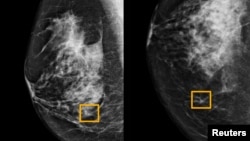

Hình vuông màu vàng cho thấy nơi hệ thống trí tuệ nhân tạo (AI) phát hiện ung thư nằm lẫn trong tế bào vú (ảnh do trường đại học Tây Bắc Chicago công bố ngày 1/1/ 2020)

Một hệ thống trí tuệ nhân tạo của Google chứng tỏ cũng điêu luyện như các chuyên viên quang tuyến trong việc phát hiện phụ nữ bị ung thư vú dựa trên hình chụp x-quang vú và chứng tỏ nhiều hứa hẹn giảm bớt sai sót, các nhà nghiên cứu tại Mỹ và Anh báo cáo.

Cuộc nghiên cứu cho thấy hệ thống AI có thể nhận ra ung thư với mức độ chính xác tương tự như các chuyên viên quang tuyến, trong khi giảm bớt các trường hợp dương tính sai khoảng 5,7% tại Mỹ và 1,2% tại Anh.

Hệ thống AI cũng giảm bớt con số những trường hợp âm tính sai, 9,4% trong nhóm tham gia tại Mỹ và 2,7% tại Anh.